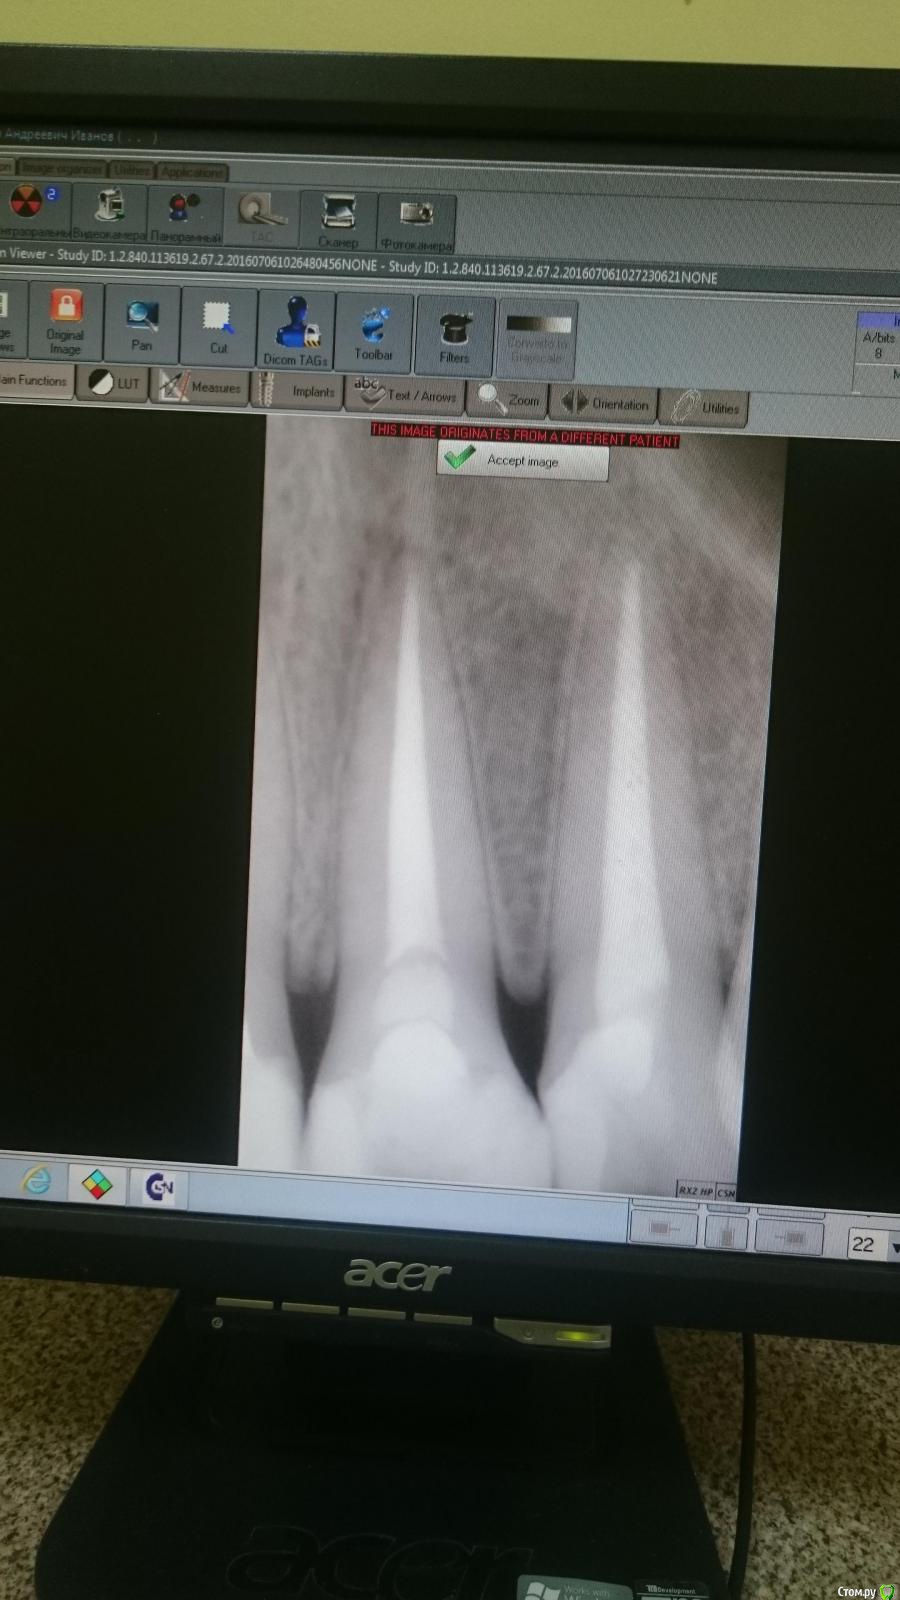

Есть два снимка (один и тот же зуб). Есть зуб, сверху него что-то темное.

На первом скриншоте зуб слева, на втором скриншоте зуб справа

post-48391-0-79456600-1467777343_thumb.jpg